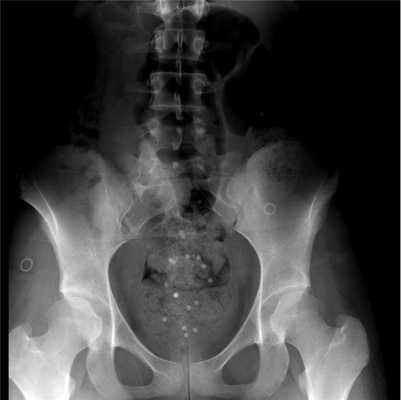

Для оценки моторики толстой кишки проведено исследование кишечного транзита с помощью рентгеноконтрастной тест-системы для диагностики хронического толстокишечного стаза (компании «Medsil»). Пациентке предложено принять внутрь 20 рентгеноконтрастных маркеров. Спустя 120 ч выполнена обзорная рентгенограмма брюшной полости: 18 маркеров располагались в ампуле прямой кишки, что свидетельствует о проктогенной причине запора (рис. 2). Тест выдавливания баллона: 5 мин (в норме 1 мин).

Рис. 2. Рентгенограмма брюшной полости больной С. через 120 ч после приема рентгеноконтрастных маркеров.